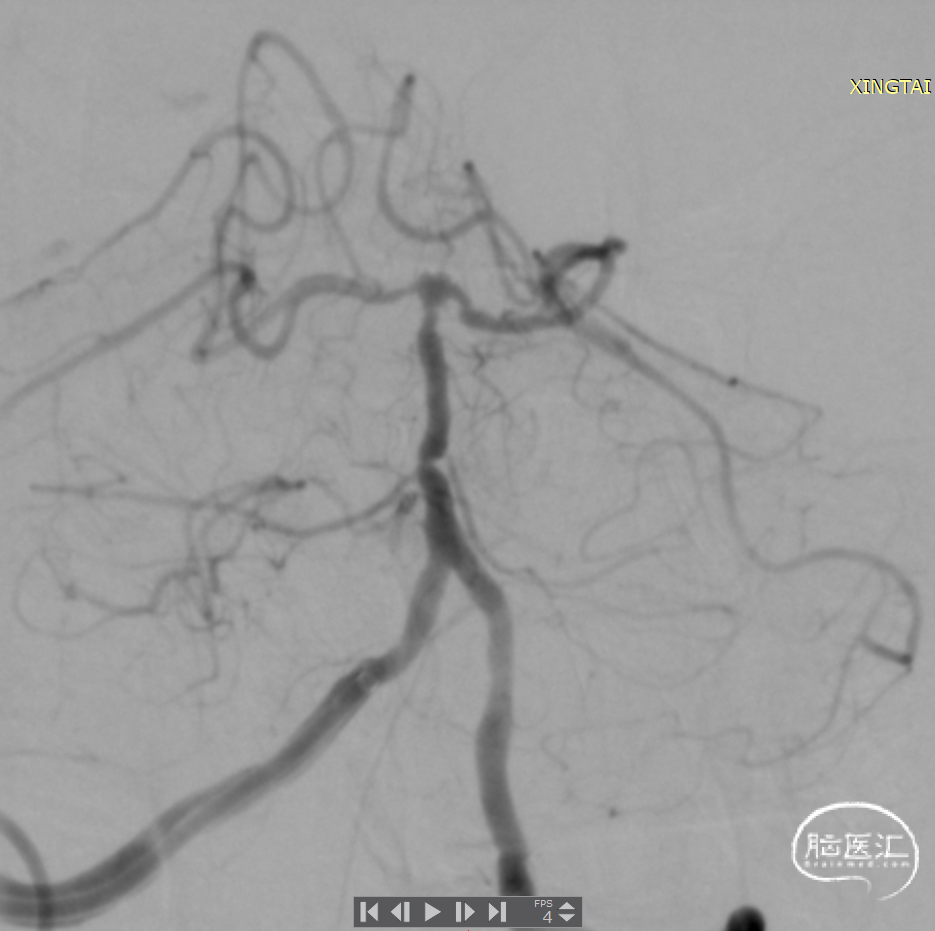

术后造影:基底动脉狭窄消失,双侧AICA通畅。

基底动脉狭窄位于双侧AICA开口处,且无双侧PICA,其供血区由双侧AICA、SCA分支代偿供血。

术中如何扩张基底动脉的同时保护双侧AICA通畅是手术成功的关键。

通桥银蛇®颅内支持导管具有优异的通过性,能够接近病变位置;具有优异的支撑性,为后续治疗器械的输送提供可靠的通路。